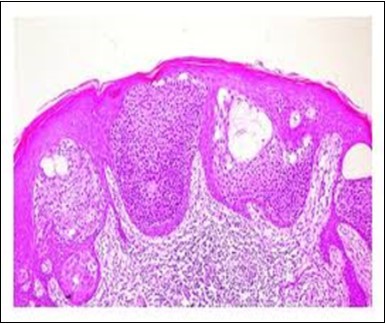

Granular arrangement of malignant cells and intercellular bridges are conspicuous with the demonstration of nuclear atypia, pleomorphism, prominent mitosis and tumour necrosis. A peripheral palisade is discernible within the cellular aggregates. Mitotic figures are common and can be quantified as up to 12 mitosis/ high power field. Tumour differentiation can prominently be of the ductal category with the demonstration of intra-cytoplasmic lumina. Comedo type tumour necrosis is evident along with foci of squamous differentiation The neoplasm is reactive to periodic acid Schiff ‘s (PAS) stain. (Figure 1, Figure 2, Figure 3, Figure 4, Figure 5, Figure 6, Figure 7, Figure 8, Figure 9, Figure 10, Figure 11, Figure 12, Figure 13.

Figure 2.Epidermal projections lined with atypical and malignant epithelial cells in eccrine porocarcinoma (14).

Figure 3.Cohesive accumulations with numerous ductular articulations of carcinoma cells in eccrine porocarcinoma (15).

Figure 4.Cellular atypia, mitosis and focal necrosis in eccrine porocarcinoma(16).

Figure 5.Sweat glandular articulations and malignant cellular aggregates with cystic spaces in eccrine porocarcinoma(17).

Figure 6.Epidermal continuity with aggregates of atypical, solid and cystic epithelial cell nests in eccrine porocarcinoma (18).